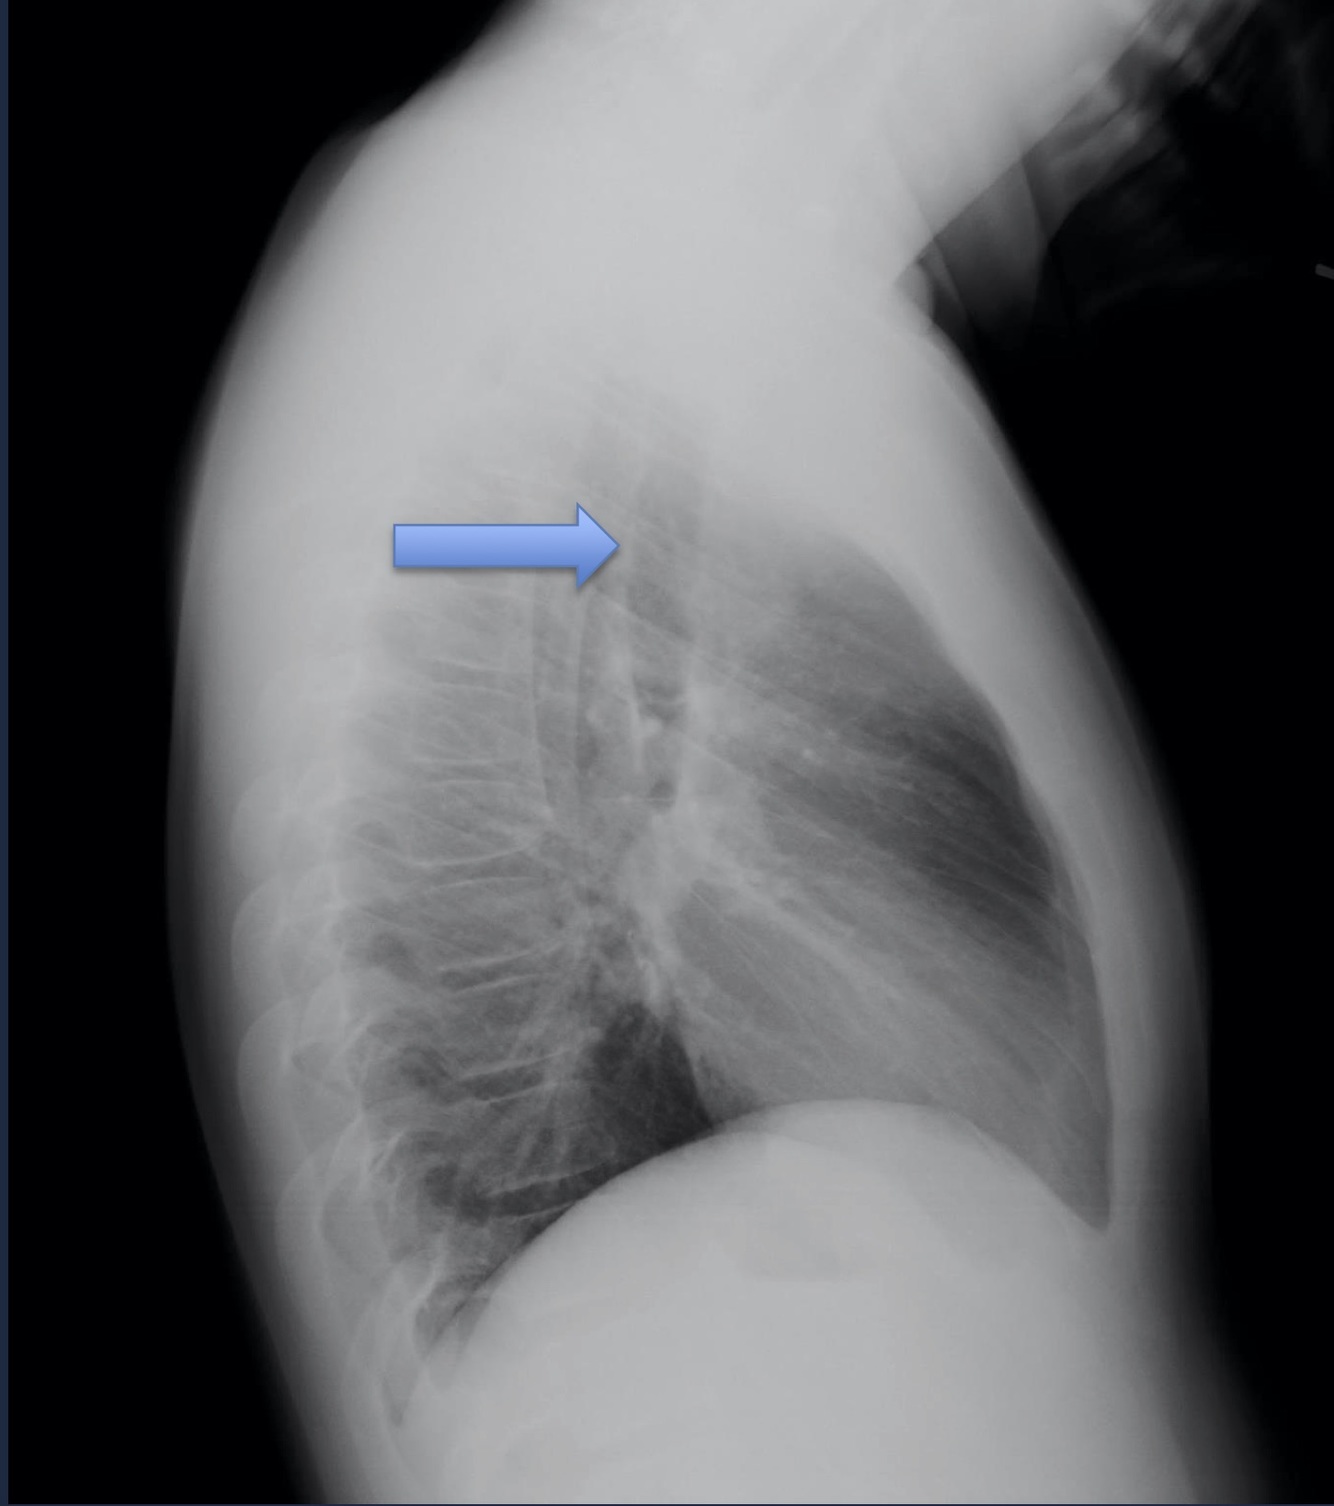

Lateral View

Can see b/l oblique fissures and horizontal fissure on the right.

Trachea